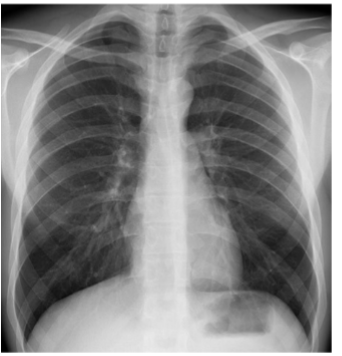

PA CXR

What is this

AP